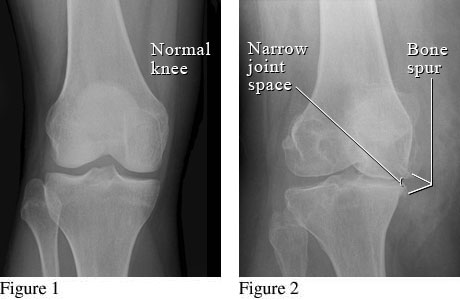

Figure 1 is an X-ray of a normal knee with normal space between the bones of the upper and lower leg. Figure 2 shows bone spurs and a narrowed joint space caused by osteoarthritis.